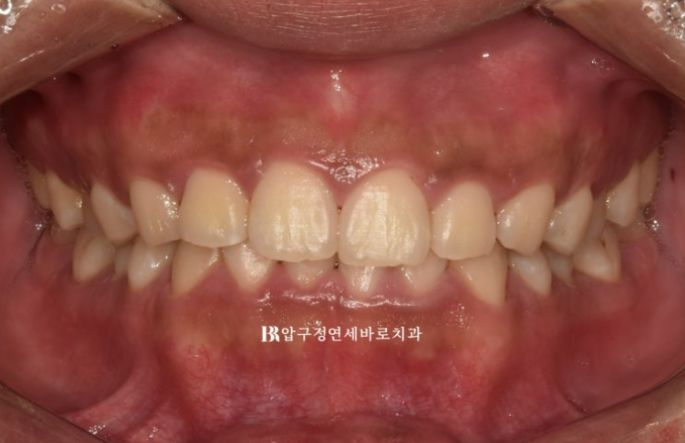

When smiling, the left teeth appear to come down lower.

The patient came in for orthodontic treatment for that reason.

When the upper teeth cover the lower teeth too much, it is called a deep bite.

The lower teeth are barely visible.

In the actual smiling photo, you can see that the occlusal plane is tilted.

The patient’s left teeth are positioned lower.